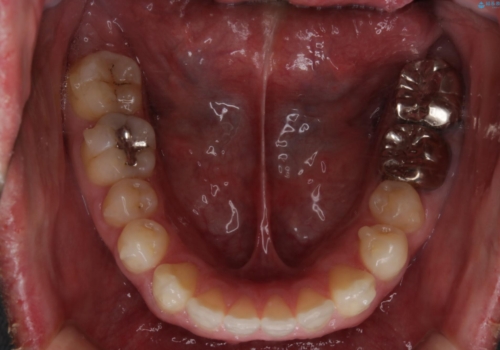

- 全体的に歯と歯の間に隙間があるのが気になるとのことで来院されました。インビザラインでの矯正治療をご希望されました。

隙間については、前歯と奥歯に多数あります。また、上下前歯は、外側に少し倒れているため隙間を閉じつつ、前歯を内側に引っ込めて並べることになりました。

インビザライン・ライトにて矯正治療を行うことになりました。